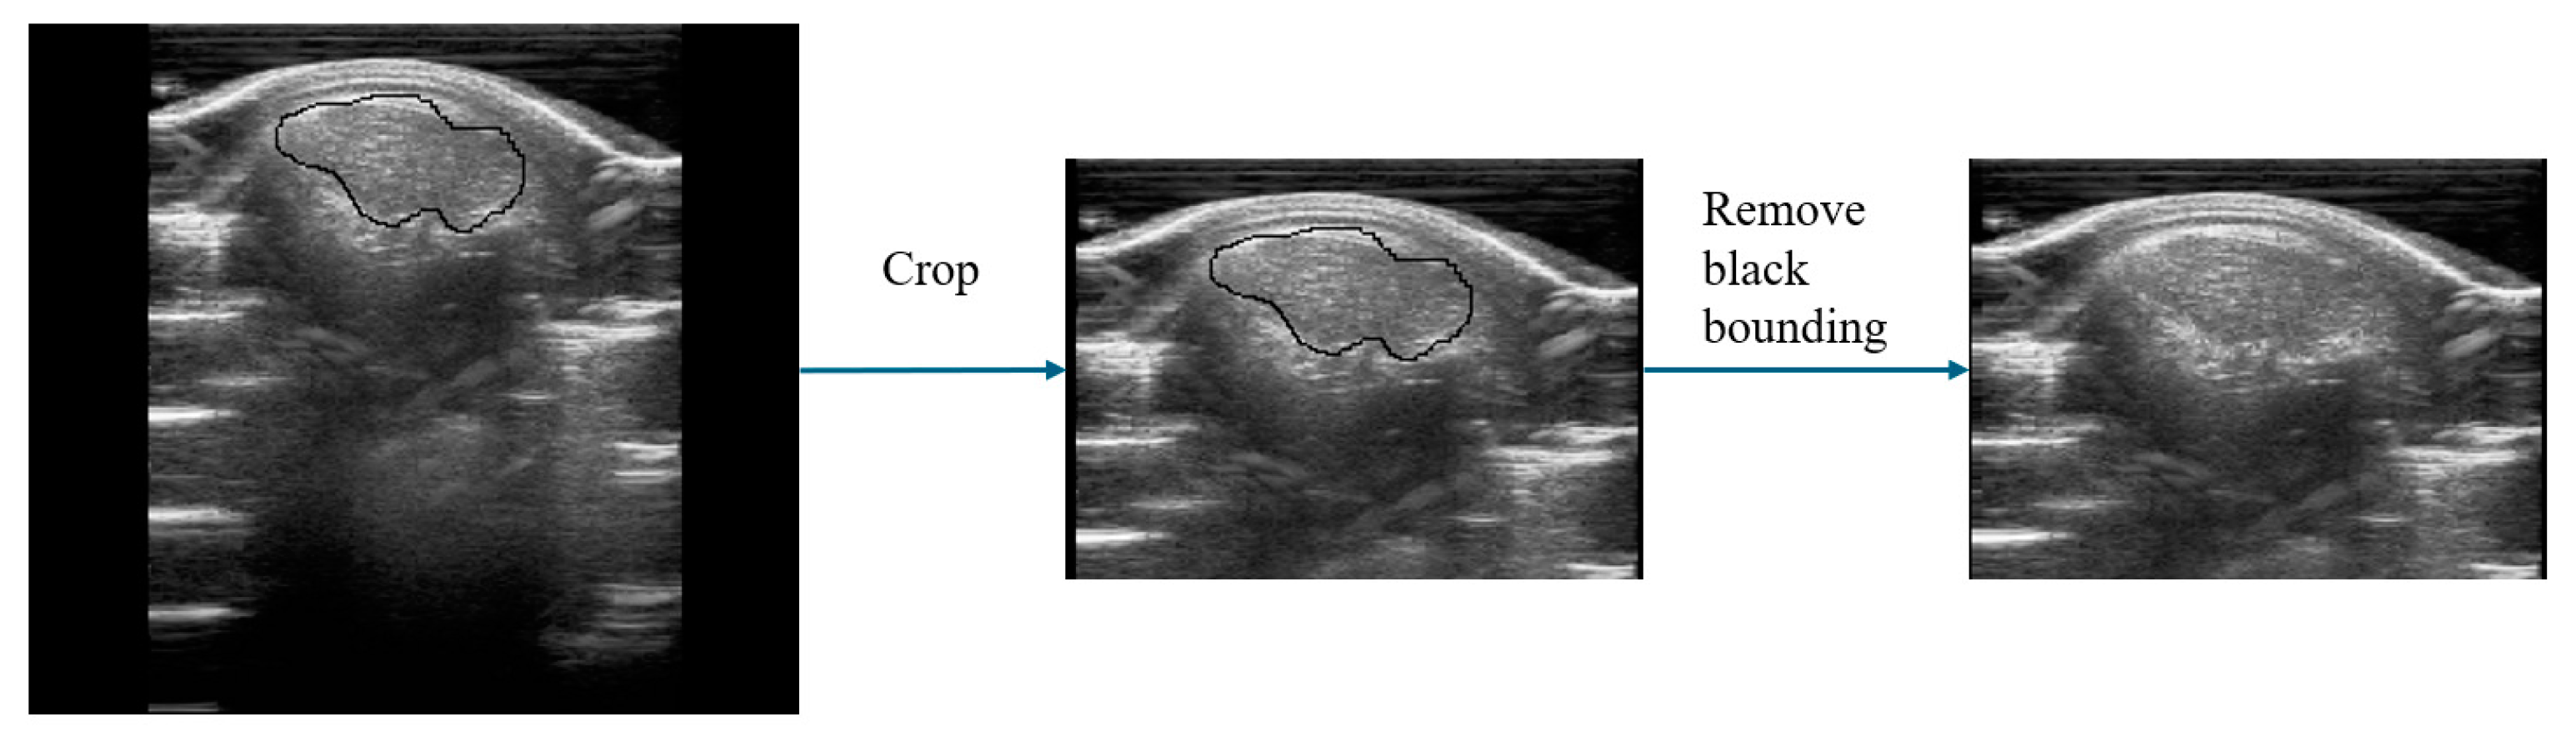

After obtaining the ROI images using the UNetPlus image segmentation model, further processing is required to input them to a multimodal prediction network, as shown in Figure 4. Image segmentation may result in black borders around the ROI images, so we used OpenCV to identify the ROI boundaries based on pixel points and then crop them.

Subsequently, to highlight features such as adipose tissue and enable better feature extraction by deep learning networks, we employed contrast-limited adaptive histogram equalization (CLAHE) [23] for adaptive contrast adjustment. This method not only helps to reduce image defects caused by segmentation but also enhances image contrast and makes details more readily visible, thus optimizing the input data for deep learning tasks.

However, the CLAHE method is only applicable to individual images. Because our experimental dataset contains images of varying brightness, we calculated the average brightness of the image pixels and normalized the brightness of all images using this value. This allowed us to mitigate instances where image brightness is excessively high or low, thus preventing significant model training errors caused by image brightness.

Figure 4. Image modal data preprocessing.